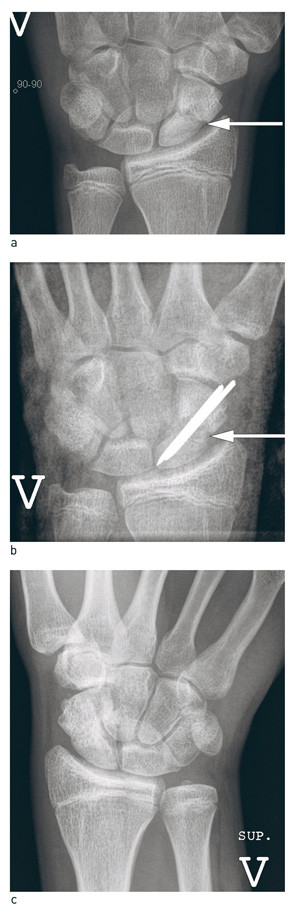

Figure 5  Treatment of scaphoid pseudarthrosis. a) 18-month old scaphoid pseudarthrosis (white arrow) in young man, b)…

Figure 5 Treatment of scaphoid pseudarthrosis. a) 18-month old scaphoid pseudarthrosis (white arrow) in young man, b) Operated with bone graft from crista and 1.6 mm smooth metal pins. Post-operative picture with cast, arrow on bone graft, c) Final check-up after 14 months. Normal wrist function, no secondary wrist arthrosis, bone graft incorporated in scaphoid